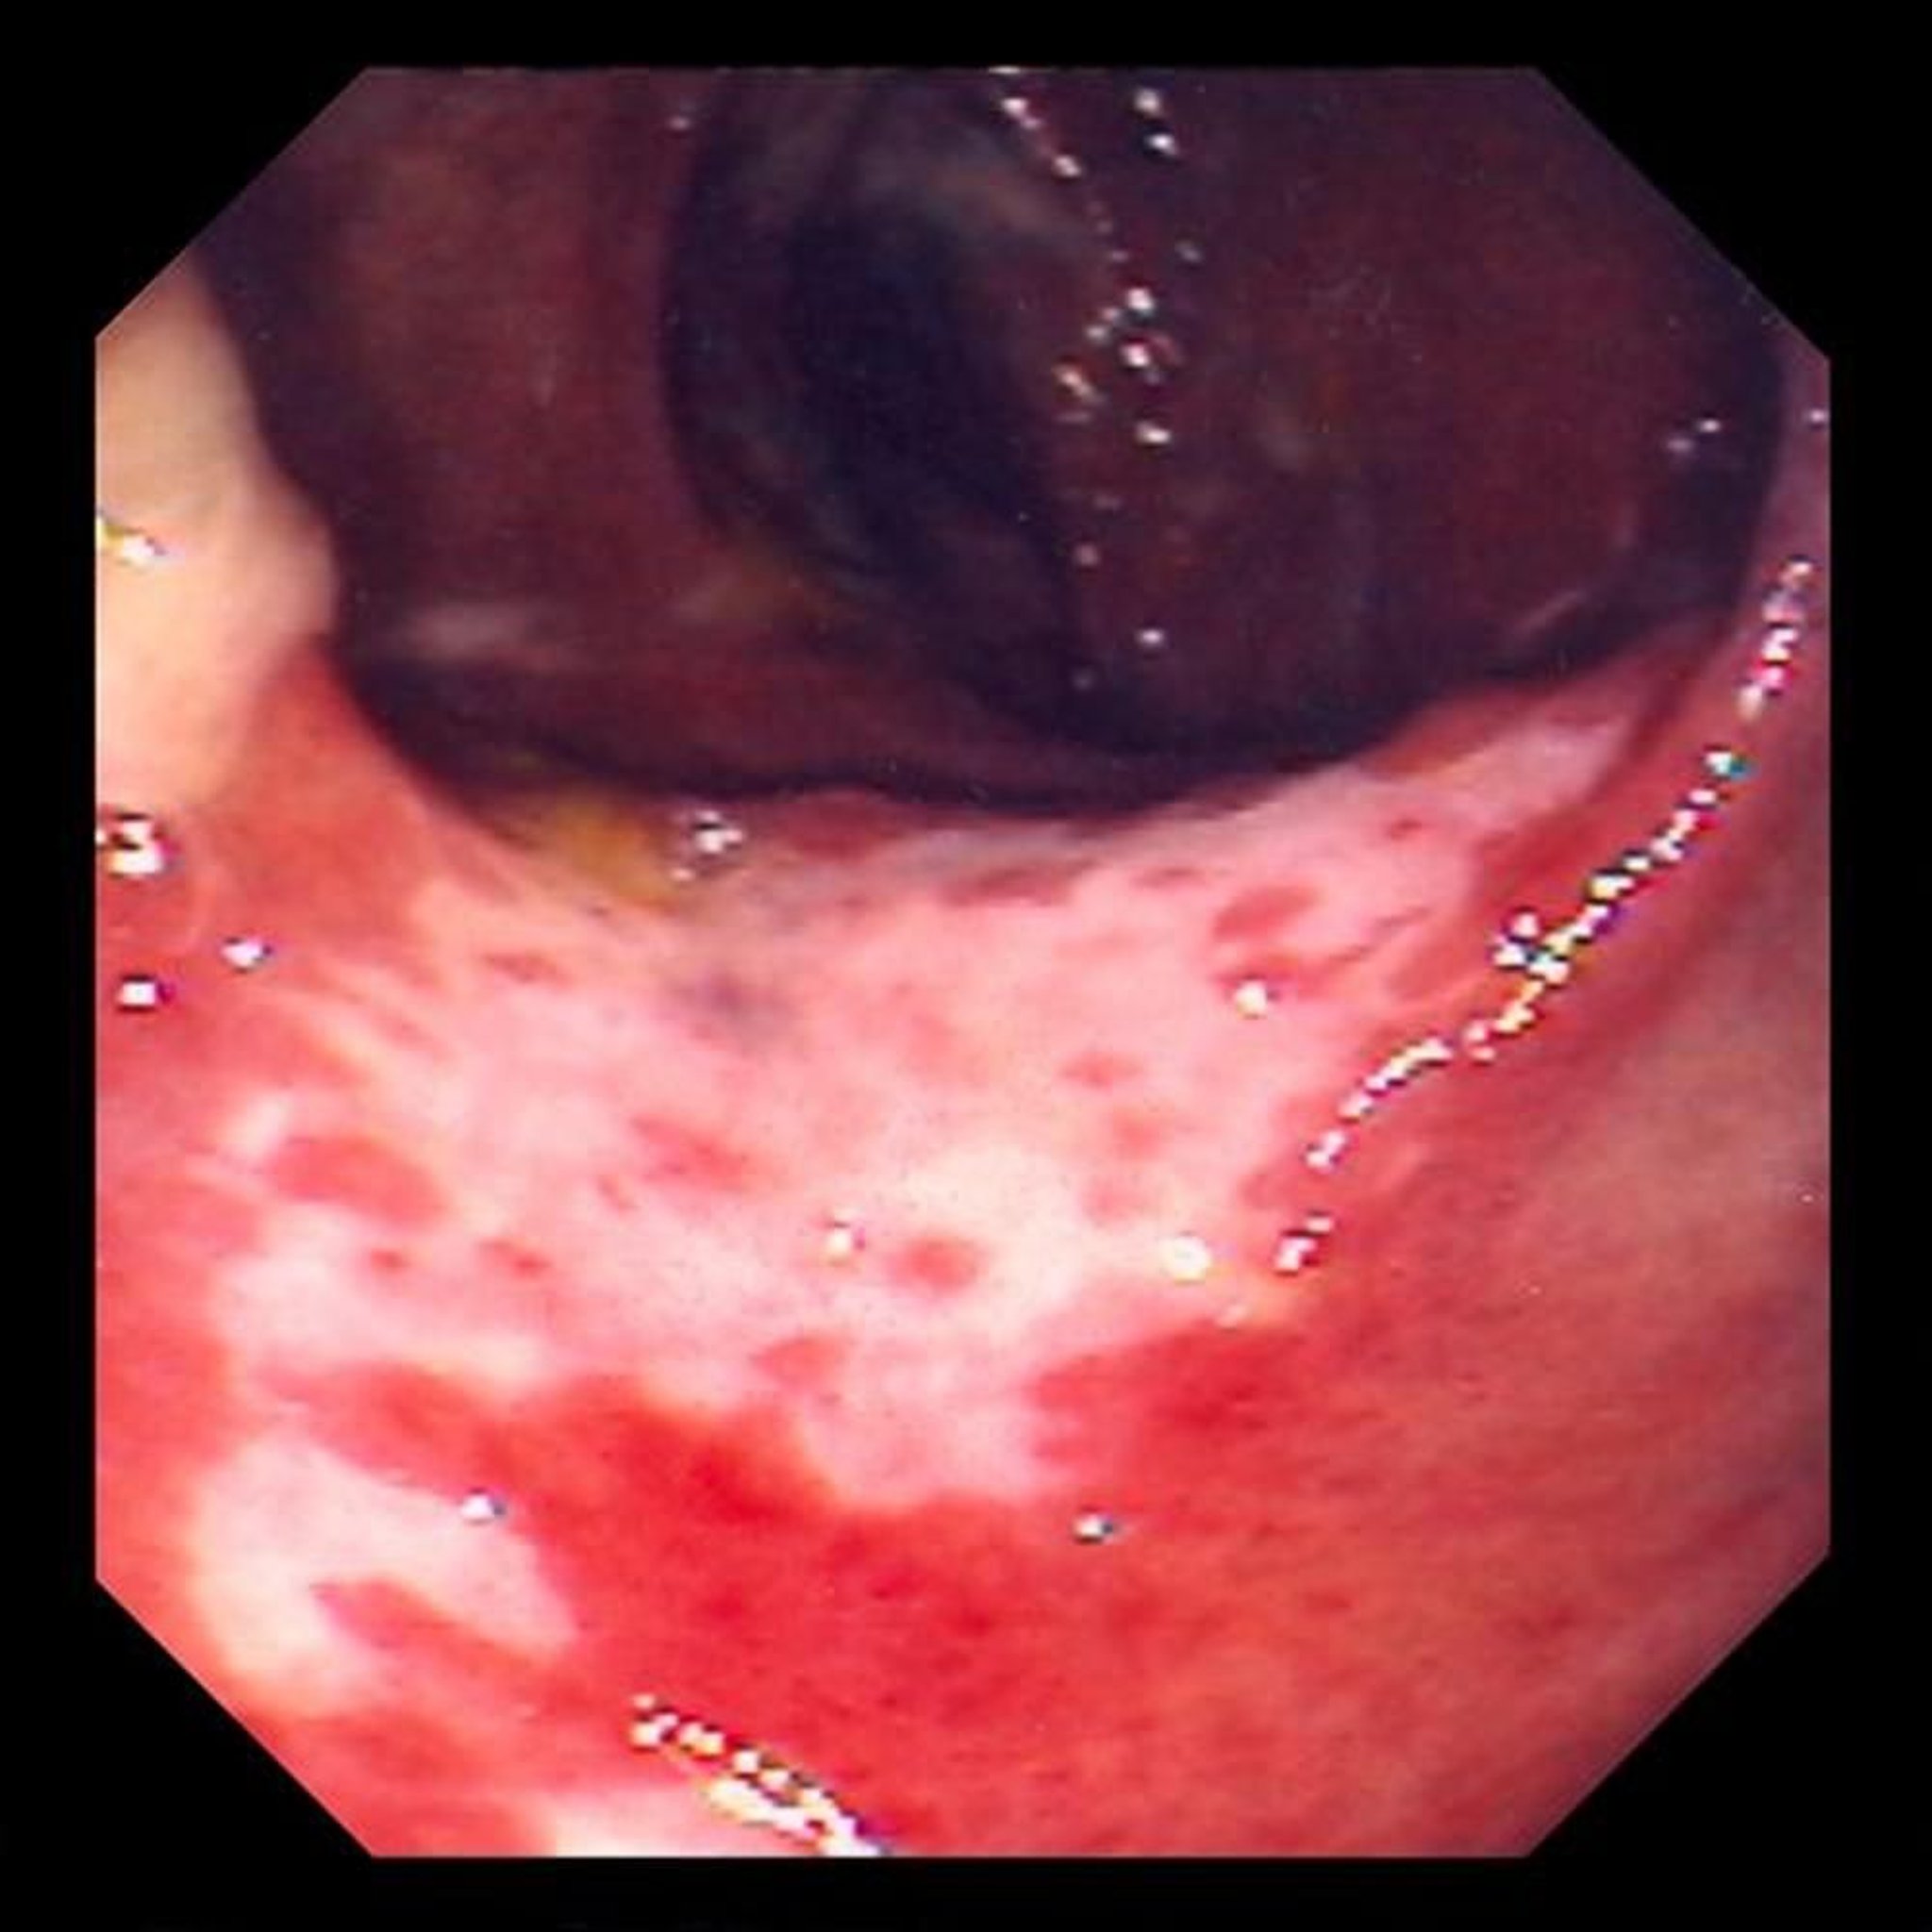

虚血性大腸炎(大腸内視鏡検査)

この写真には、血流が遮断されたために腸の粘膜に生じた損傷が写っています。腸の粘膜が赤くなって、潰瘍(白い部分)で覆われています。

Photo provided by David M. Martin, MD.